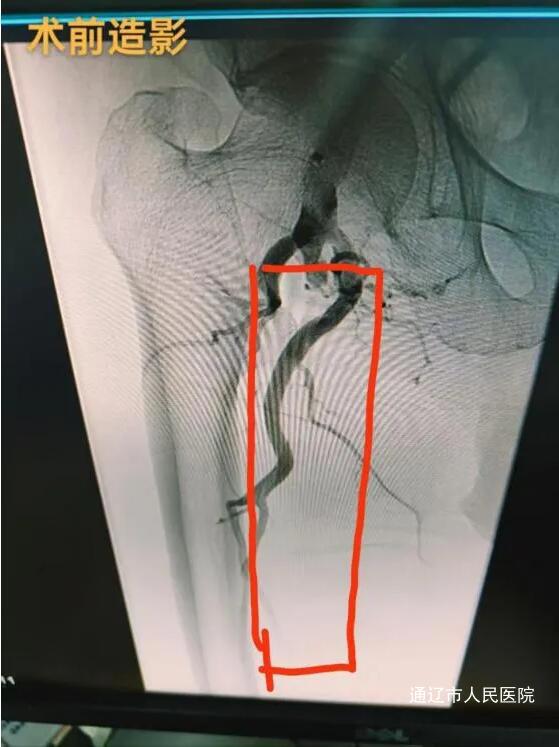

患者,男性,79岁。术前检查发现,其双侧下肢动脉广泛存在动脉粥样硬化,多处混合及钙化斑块致使管腔轻至中度狭窄,右侧股动脉更是出现长达20cm的闭塞段。患者自述,自2022年起就饱受双下肢间歇性跛行的困扰,症状逐年加重。一个月前刚接受左侧髂、股、腘动脉支架置入及下肢动脉PTA。面对这一复杂病情,我院血管肿瘤介入科魏东升主任团队迅速行动,凭借丰富的临床经验与严谨的专业态度,精心制定了个性化的治疗方案。手术由梁羽副主任医师主刀,那日苏、张贺然医师担任助手。手术过程中,医疗团队展现出了高超的技术水平与默契的协作能力。他们通过逆行穿刺左侧股总动脉,精准操作导丝穿越病变区域,完成正逆向开通会师,并在远端成功放置保护伞。随后,启用JetStream旋切系统,将斑块切削并吸出体外,实现血管减容,之后配合药物球囊扩张,结合药物洗脱支架置入,成功打通患者堵塞的血管。术后第二天,患者便能下地行走,间歇性跛行症状明显改善,手术取得了显著成效。